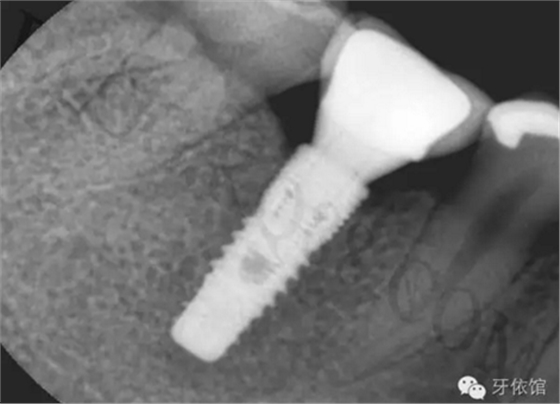

術(shù)后三個月的X光片。

再將烤瓷冠就位,拍X光片,檢查烤瓷牙與基臺之間是否密貼。